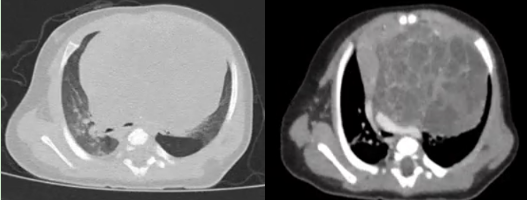

近日,一名僅2月齡、體重只有5.2kg的男嬰,因胸悶、呼吸困難來華西醫(yī)院小兒外科徐暢主任醫(yī)師處就診。經(jīng)CT檢查發(fā)現(xiàn),其縱隔內(nèi)有一個(gè)巨大腫塊,最大直徑 7.4×6.0cm,像胸腔里長(zhǎng)一個(gè)巨大的“石榴”,嚴(yán)重壓迫心臟、左主支氣管及肺動(dòng)脈,不盡快摘除,隨時(shí)可能引發(fā)呼吸循環(huán)衰竭,危及生命。

患兒胸部CT影像